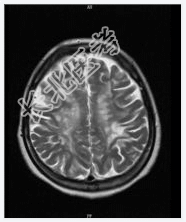

- [材料题] 患者女,28岁,反复左下肢无力4年余,痛觉减退2月余。查体:神清,左局部触觉减弱,左下肢肌力Ⅳ级,双巴氏征(+)。2001年MR示:脑脱鞘改变。行头颅MR平扫。

- 简答题1、诊断及依据是什么?

- 简答题2、鉴别诊断有哪些?